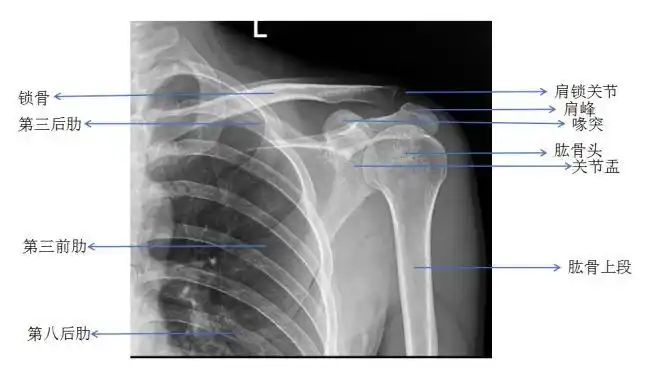

大部分医生都会让患者做肩关节dr正侧位检查肩关节情况